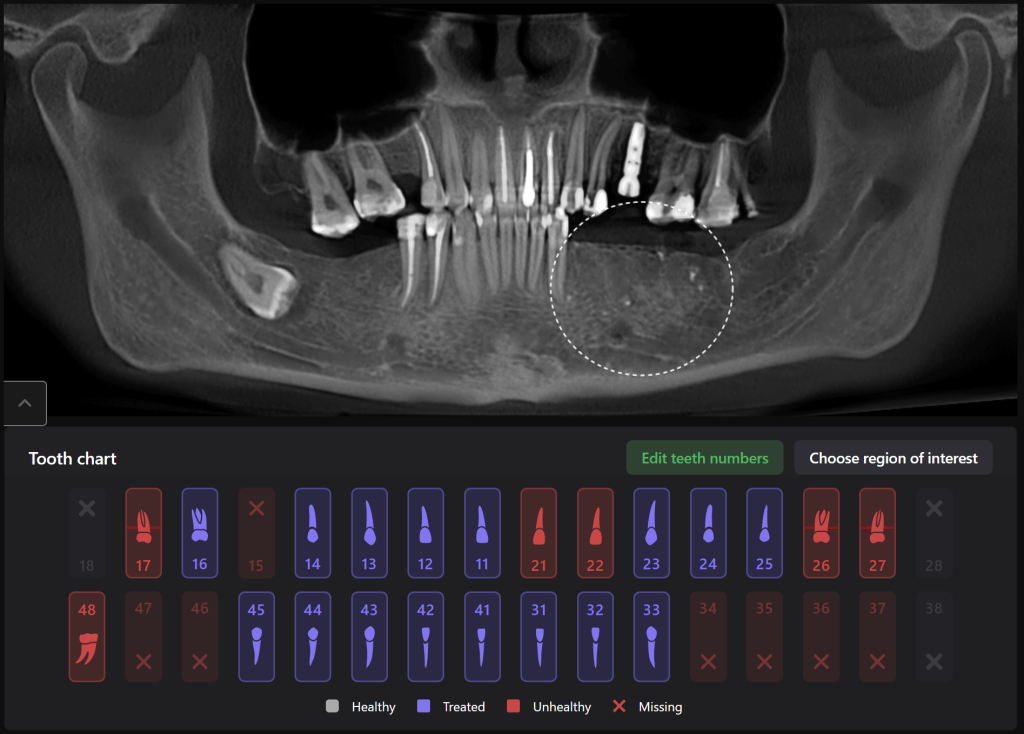

Panoramic reconstruction from CBCT